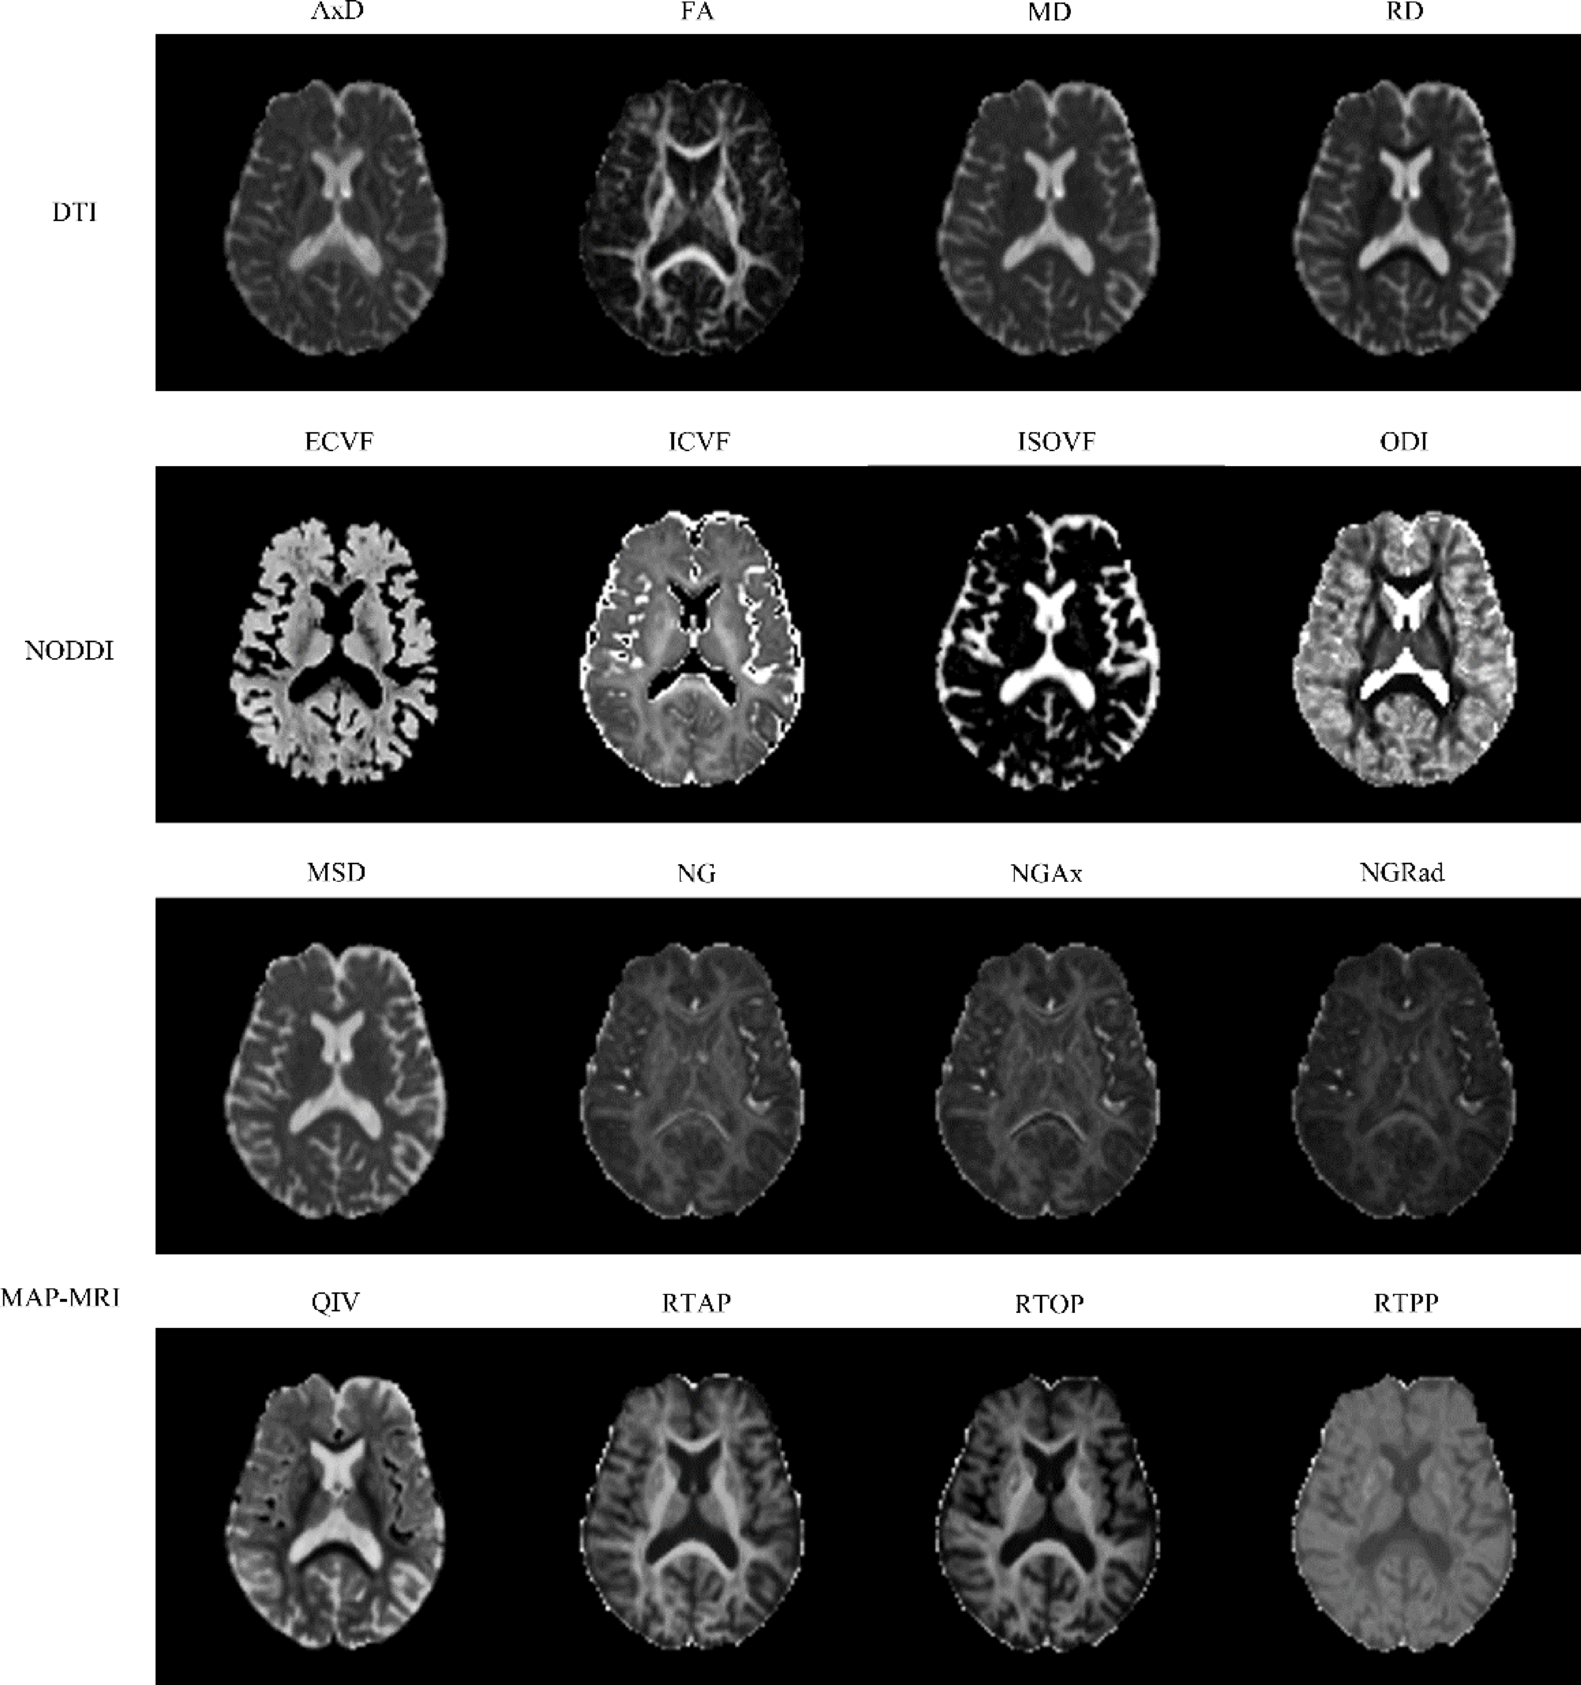

Fig. 1

From: Analysis of advanced diffusion models assessing white matter microstructure in Alzheimer’s disease

Comparison of three diffusion MRI maps revealing brain microstructure. The top image presents DTI parameters, including axial diffusivity (AxD), fractional anisotropy (FA), mean diffusivity (MD), and radial diffusivity (RD). The middle image displays NODDI parameters: extracellular volume fraction (ECVF), intracellular volume fraction (ICVF), isotropi volume fraction (ISOVF), and orientation dispersion index (ODI). The botto image shows MAP-MRI parameters: mean squared displacement (MSD), non-Gaussianity (NG), axial non-Gaussianity (NGAx), radial Non-Gaussianity (NGRad), Q-space inverse variance (QIV), return-to-axis probability (RTAP), return-to-origin probability (RTOP), and return-to-plane probability (RTPP). Each parameter map reveals specific aspects of brain tissue microstructure.